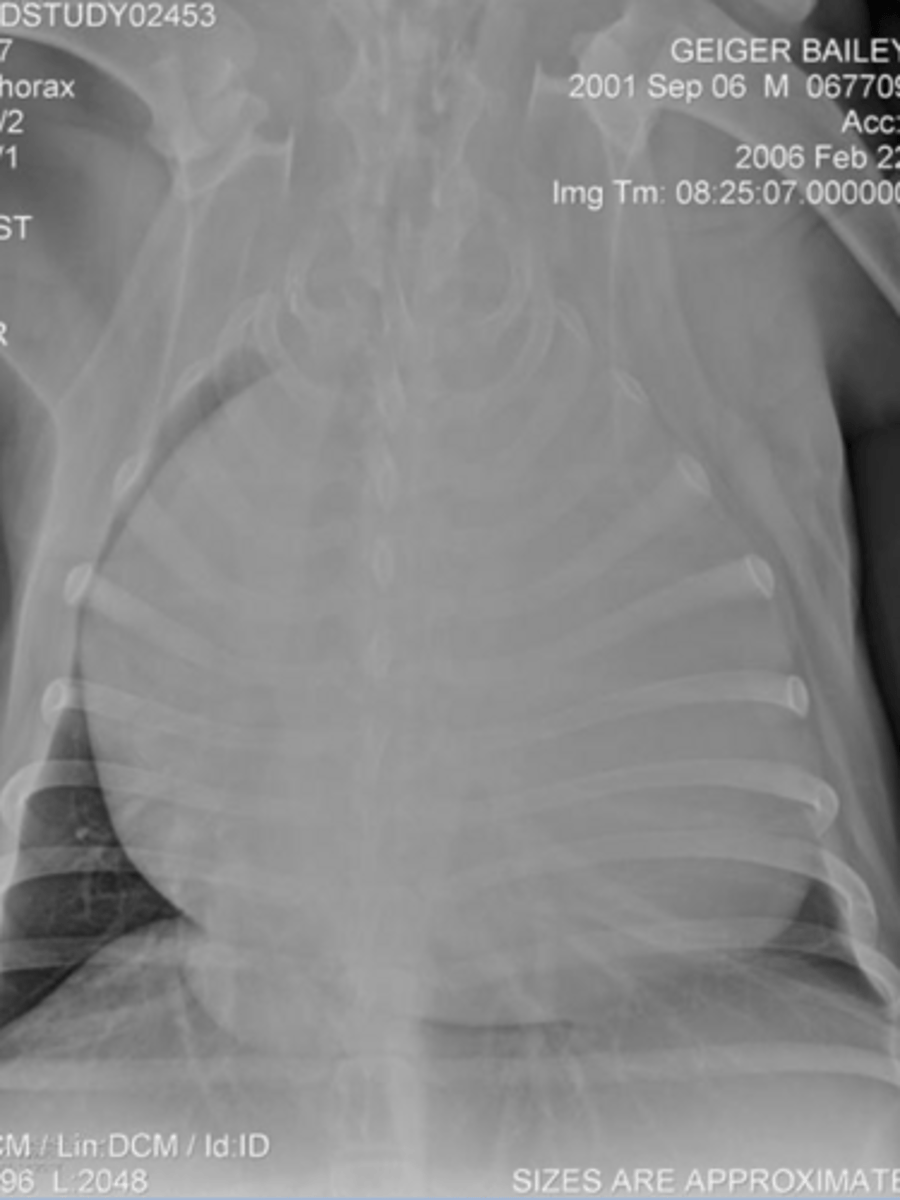

5.7 + 4.3 = 10

(K9 - 10.5)

Given the following radiograph do we have an enlarged heart?

No